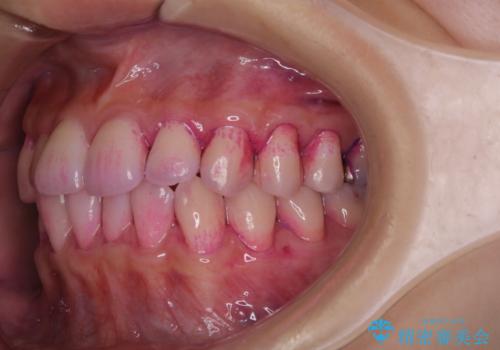

表のワイヤー矯正治療中にPMTCで綺麗に